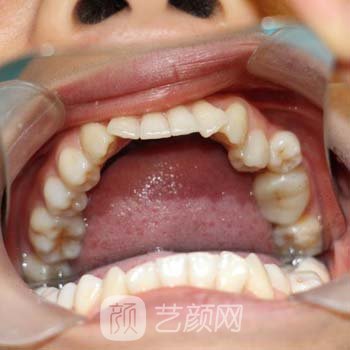

从小在农村长大,每天跳上跳下。我对美学、面子、牙齿不整洁的外表和咬合问题没有太多的想法,这些都没人关心,我的父母也不理解。我换了牙后,牙齿变得拥挤不平。这个丑陋的牙齿陪伴了我20多年。事实上,当我在大学的时候,我有点讨厌我的牙齿。我想去牙齿的矫正医院做手术。

到了面诊的时间,我来到了西安交通大学口腔医院。医院规模大,环境舒适,医护人员服务很好。当时,我面对的医生,是一位态度友好的美丽医生。经过医生仔细检查,我的牙齿,牙齿,和我一样,可以通过戴牙套来矫正,这不仅可以解决牙齿,的不规则性问题,还可以解决咬合问题。医生向我推荐了几种牙套,包括隐形牙套、半隐形牙套和金属支架牙套。因为手头资金有限,我选择了经济型金属支架牙套。

医生说,选择金属剥离牙套的人不少,矫正的果特别好。在选择牙套后,医生为我的牙齿做了一个简单的矫正。在拔掉两个拥挤的牙齿,后,这里的一些孩子会问我拔牙时是否疼。其实我当时就害怕了。被下药后,拔牙时没有疼痛。嘻嘻,别怕。

两个星期后,我来到医院。医生给我戴上牙套。当我第一次穿上它们的时候,我觉得牙齿有点紧绷和疼痛。经过几天的适应,我好多了。医生告诉我,当我戴牙套的时候,这些天我不能吃任何又冷又硬的东西。我每天早晚刷牙漱口,以保持牙齿干净。矫正将持续一年多,这一变化较为漫长,不可能一蹴而就。

一年半过去了,我回到了医院。医生脱下了我的牙套,护士给我拿来了一面小镜子。看着镜子里整洁白皙的牙齿,我抱着护士跳了起来,牙齿变得美丽起来。我也变得喜欢说笑,也喜欢交朋友。朋友说我从里到外就像变了一个人。